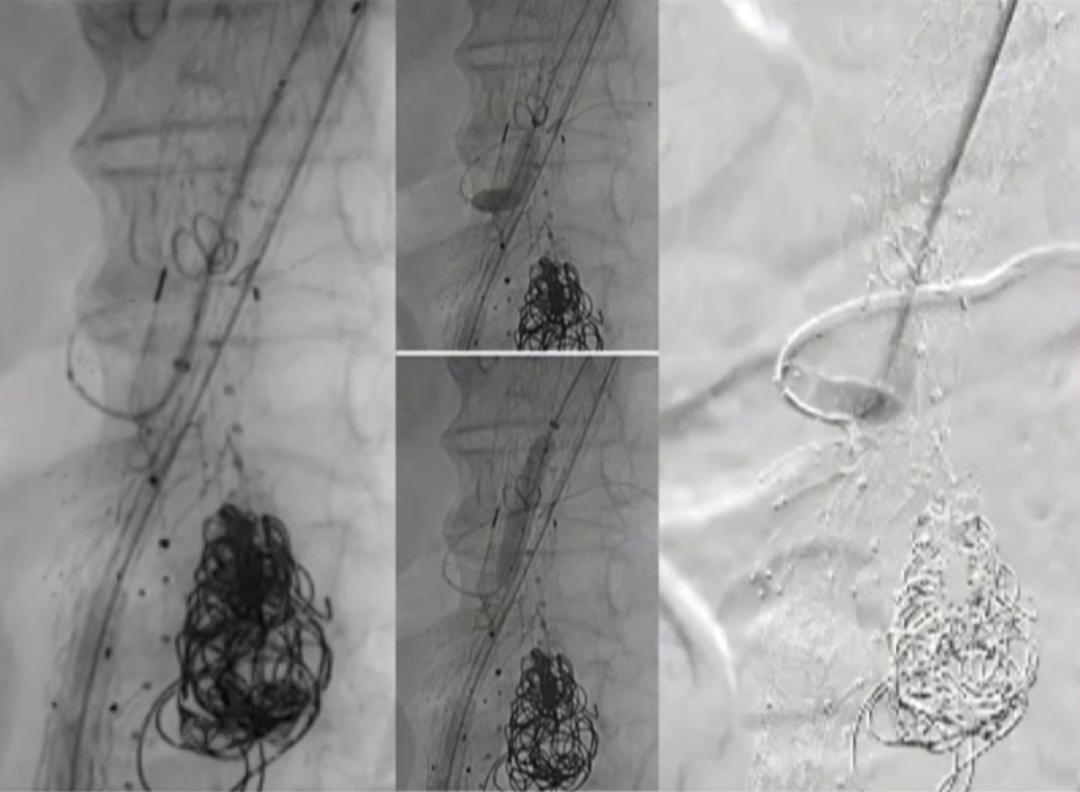

超选SMA,桥接8-100mm Viabahn,内衬8-60mm Absolute裸支架

超选CA,桥接8-100mm Viabahn

超选RRA烟囱支架,桥接6-100mm+6-50mm Viabahn

超选LRA烟囱支架,桥接6-100mm Viabahn

右侧:16-16-140mm Excluder髂腿;

左侧:16-16-120mm Excluder髂腿

术后造影